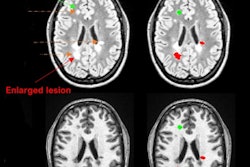

Metabolic maps showing the ratio of myo-inositol to N-acetylaspartate (mI/NAA) clearly depict small subcortical or juxtacortical lesions (circles) that appear inconspicuous at T1-weighted MRI (T1w)/fluid-attenuated inversion-recovery (FLAIR) imaging.The group found the following brain differences in patients with MS:

- Lower levels of an amino acid derivative called N-acetylaspartate, which is associated with compromised integrity of neurons

- Higher levels of myo-inositol, which is involved in cell signaling; increased levels indicate significant inflammatory disease activity